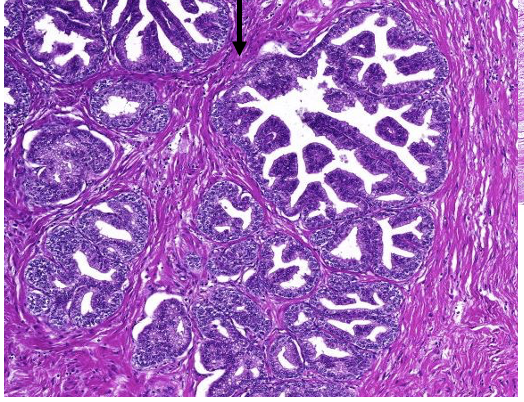

welk orgaan

prostaat hypertrofie

pathologische kenmerken prostaat hypertrofie

ipv lobulaire—> nodulaire indeling, omgeven door bindweefsel

bevat gedilateerde klierbuizen

vorming van cysten (cysteuze dilatatie)

toename stroma, glad spierweefsel en lymfocyten